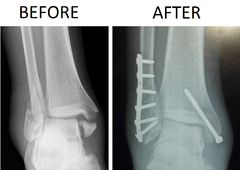

A trimalleolar fracture is a fracture of the ankle that involves the lateral malleolus, the medial malleolus, and the distal posterior aspect of the tibia, which can be termed the posterior malleolus. The trauma is sometimes accompanied by ligament damage and dislocation.[1]

Surgical repair utilizing open reduction and internal fixation is generally required, and because there is no lateral restraint of the foot, the ankle cannot bear any weight while the bone knits. This typically takes six weeks in an otherwise healthy person but can take as much as twelve weeks. Non-surgical treatment may sometimes be considered in cases where the patient has significant health problems or where the risk of surgery may be too great.[1]